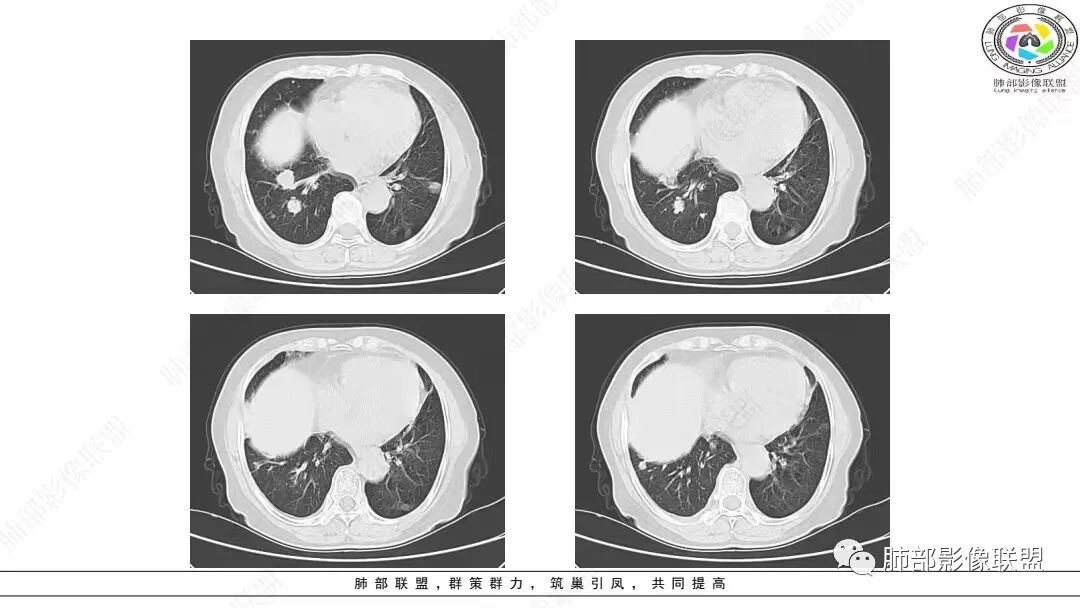

2.影像学特点:右肺上叶前段胸膜下不规则较大团块影,边界清楚欠光整,浅分叶,肺血管支气管出入,边缘膨隆胸膜凹陷具有一定张力,未见典型粗短毛刺,部分围以边界清楚的磨玻璃影,灶周小叶间隔增厚。块影密度不均,渐进性强化,可见砂砾样钙化,未见明显液化坏死或空洞。增强后病灶显示渐进性强化。MIP显示病灶内肺动脉穿行、并部分肺动脉受侵变细。纵隔及右锁骨上(胸廓入口)见肿大淋巴结。两肺可见多发大小不一的结节影,边界清楚,随机分布。

多数学者认为血管支气管包埋征是肺LELC的特征性表现。本组41.97 0A(81/193)病灶内部动脉期见血管包埋征,而血管形态正常,无明显受侵、狭窄,与上述研究报道相符,可能提示肺LELC具有类似淋巴瘤相似的特点,即易浸润周围结构,引起间质增厚、肺泡壁破坏及肺泡腔充盈,但较少侵犯血管[1 3|。但本组108例(108/193,55.96%)表现为血管受侵、狭窄,75.82%支气管受累狭窄闭塞,可能提示肺LELC病灶内血管受侵狭窄及支气管破坏较淋巴瘤更多见[1 3|,较大肺LELC病灶更易出现血管、支气管受侵、破坏。

本组97.13%病变累及胸膜,大部分病灶(75.41%)与纵隔关系密切,表现为靠近肺门或紧贴纵隔胸膜生长,多数病灶与纵隔胸膜之间有脂肪间隙存在。    111例(111/244,45.49%)显示“类胸膜尾征”改变,即肿瘤紧贴胸膜生长、增厚,但未突破胸膜向外生长,与正常胸膜的夹角呈钝角,在纵隔窗上呈现类似脑膜瘤的脑膜尾征样改变;推测其形成机制可能是肺LELC的生物学行为具有一定恶性,易侵犯胸膜,使胸膜增厚逐渐延伸,但其恶性度低于肺鳞癌、腺癌,较少直接导致胸膜不均匀增厚甚或突破胸膜向外生长。

本组50.82%(124/244)病灶周围见磨玻璃密度影改变,33.20%在磨玻璃密度影中伴有小叶间隔的间质增厚,表现为小叶间隔网格状增粗,但不伴有串珠状排列的小结节;其形成机制可能是肿瘤周围实质及间质均伴有大量淋巴细胞浸润以及小叶间隔的淋巴管扩张,而肺腺癌或鳞癌的癌性淋巴管炎多表现为小叶间隔结节状增厚,可呈串珠状改变。上述征象可作为肺LELC与肺鳞、腺癌的鉴别点。